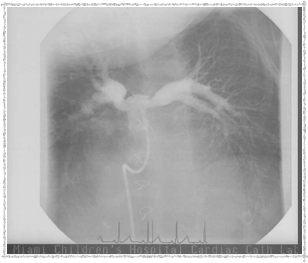

Second Catheterization — Dr. Danyal Khan

In 2010, Elyse underwent her second catheterization procedure, overseen by Dr. Danyal Khan at Miami Children's Hospital. The procedure focused on her pulmonary arteries, and these images show the before and after.

2010 - Before Procedure

Before the procedure